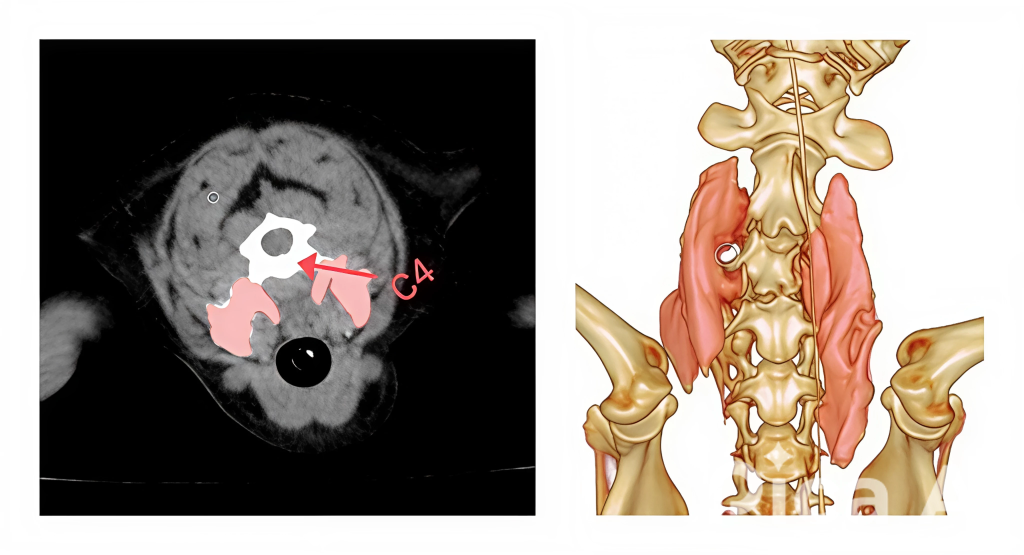

Блокада лестничной мышцы на примере операции, проведенной у 7-летней собаки породы французский бульдог (вес 11 кг) по поводу декомпрессии спинного мозга, вызванной экструзией области С4-С5. Пациент поступил в клинику с сильно выраженным болевым синдромом в области шеи, собака при поворотах головы в стороны сжимала шею, вокализировала и дрожала, также при осмотре отмечался спастический гемипарез по левой стороне грудной и тазовой конечностей.

Для визуализации распределения местного анестетика было проведено компьютерно-томографическое (КТ) исследование с использованием йогексола (4:1) в качестве контрастного вещества. Результаты КТ показали хорошее распределение анестетика в краниальном и каудальном направлениях (рис. 8), а также широкую площадь проникновения по целевым фасциальным структурам.

Для выполнения данной хирургической манипуляции, помимо общей анестезии, индуцированной пропофолом и поддерживаемой ингаляционной анестезией с помощью изофлурана, была проведена блокада лестничной мышцы под контролем УЗИ (видео 2). Техника выполнения блокады лестничной мышцы схожа с методикой блокады длинной мышцы головы за исключением необходимости идентифицировать четвертый шейный позвонок с краниальной его части, при этом целевой точкой будет вентральный бугорок поперечного отростка С4. Он визуализируется как акустическая тень от кортикального слоя вентрального бугорка, направленная перпендикулярно к поверхности сканирования. Над бугорком определяется структура, напоминающая «шапочку», которая является лестничной мышцей.

Возможны два подхода к проведению блокады (рис. 9). Введение спинальной иглы может осуществляться с дорсальной или вентральной стороны датчика. При первом подходе игла направляется до соприкосновения с вентральным бугорком между вентральной частью лестничной мышцы и длинной мышцей головы. Введение местного анестетика в этой зоне предполагает более вентральное его распределение. При втором подходе, когда игла направляется с дорсолатеральной поверхности шеи, точкой введения анестетика будет дорсальная часть лестничной мышцы рядом со средними межпоперечными мышцами. При выполнении такой инъекции на УЗИ можно обратить внимание, как анестетик стекает в сторону, к месту выхода спинномозгового нерва из межпозвоночного отверстия. На рис. 10 красной точкой отмечено место введения анестетика на КТ-скане третьего шейного позвонка.